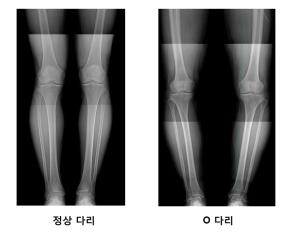

¹«¸­ ÅëÁõ ȯÀÚ 2¸í Áß 1¸í O´Ù¸®

[¿Óóµ¥Àϸ®] XÀÚ·Î ºñ¶Ô¾îÁö°í,OÀÚ·Î ÈØ ´Ù¸®´Â º¸±â¿¡µµ ¾È ÁÁÀ» »Ó¸¸ ¾Æ´Ï¶ó ¹«¸­ °Ç°­¿¡ ÁÁÀº ¾ÊÀº ¿µÇâÀ» ¹ÌÄ£´Ù. ¹Ý´ë·Î ¹«¸­ÀÌ ¾ÆÇ »ç¶÷À̶ó¸é ÀÌ °°Àº ´Ù¸® º¯ÇüÀÌ ÁúȯÀ» ´õ¿í ¾ÇÈ­½Ãų ¼ö ÀÖ¾î ¹Ýµå½Ã Ä¡·áÇØ¾ß ÇÑ´Ù.

º¸°Çº¹ÁöºÎ ÁöÁ¤ °üÀý Àü¹® ¹Ù¸¥¼¼»óº´¿ø Á¶»ç °á°ú ¹«¸­ ¾ÆÇ »ç¶÷ 2¸íÁß 1¸íÀÌ¡®O´Ù¸®¡¯ÀÎ °ÍÀ¸·Î ³ªÅ¸³µ´Ù. ¶ÇÇÑ O´Ù¸®·Î Áø´ÜµÈ »ç¶÷µéÀº ´ëºÎºÐ ¹«¸­ ¿¬°ñ ¶Ç´Â ¹Ý¿ù»ó ¿¬°ñÆÇÀÇ ¸ö ¾ÈÂÊ ºÎÀ§°¡ ¸¹ÀÌ ¼Õ»óµÅ ¼ö¼úÀÌ ÇÊ¿äÇÑ °ÍÀ¸·Î È®ÀεƴÙ.

¹Ù¸¥¼¼»óº´¿ø °üÀý¼¾ÅÍ(¿©¿ìÁø °üÀý¼¾ÅÍ ¼ÒÀå)°¡ Áö³­ÇØ 7¿ùºÎÅÍ 11¿ù±îÁö ¹«¸­ ÅëÁõÀ¸·Î º´¿øÀ» ã¾Æ ´Ù¸® X¼±À» ÃÔ¿µÇÑ È¯ÀÚ 500¸íÀ» ºÐ¼®ÇÑ °á°ú, ÀüüÀÇ 50.6%ÀÎ 253¸íÀÌ O´Ù¸®, 4.8%ÀÎ 24¸íÀÌ¡®X´Ù¸®¡¯¿´À¸¸ç, 44.6%(223¸í)´Â Á¤»óÀ¸·Î Á¶»çµÆ´Ù.

O´Ù¸®ÀÇ Áø´ÜÀº °í°üÀý°ú ¹«¸­ °üÀý, ¹ß¸ñ °üÀýÀÇ Áß½ÉÀ» ÀÌÀº ¼öÁ÷¼±À» ±âÁØÀ¸·Î Çã¹÷Áö »À°¡ ¹ú¾îÁø ¼±°ú Á¾¾Æ¸®»À°¡ ¹ú¾îÁø ¼±ÀÌ ÀÌ·ç´Â °¢µµ°¡ 3µµ¸¦ ³ÑÀ» Á¤µµ·Î ¸ö ¹Ù±ùÀ¸·Î ÈØ °ÍÀÌ´Ù. O´Ù¸®·Î Áø´ÜµÈ »ç¶÷ Áß 79¼¼ ¿©¼ºÀº ÀÌ °¢µµ°¡ 20µµ¸¦ ³ÑÀ» Á¤µµ·Î ½ÉÇß´Ù.¡®X´Ù¸®¡¯´Â ¹Ý´ë·Î ´Ù¸®°¡ ¸ö ¾ÈÂÊÀ¸·Î ÈØ °ÍÀ» ¸»ÇÑ´Ù. ¹Ù¸¥¼¼»óº´¿ø ¼­µ¿¿ø ¿øÀå(Á¤Çü¿Ü°ú, ÀçȰÀÇÇаú Àü¹®ÀÇ)Àº¡°O´Ù¸®´Â ¹Ì°ü»ó ÁÁÁö ¾ÊÀ» »Ó¸¸ ¾Æ´Ï¶ó, ¹æÄ¡Çϸé üÁßÀÌ ¹«¸­ °üÀýÀÇ ¾ÈÂÊ ºÎÀ§¿¡¸¸ °úµµÇÏ°Ô ÁýÁߵǸ鼭 ¹«¸­ÀÇ ¹Ý¿ù»ó ¿¬°ñÆÇÀ̳ª ¿¬°ñÀÇ ³»Ãø ¼Õ»óÀÌ ÁýÁß ¹ß»ýÇϰí, °á±¹ ÅðÇ༺°üÀý¿°À¸·Î ÁøÇàµÉ ¼ö ÀÖ´Ù¡±°í °æ°íÇß´Ù.